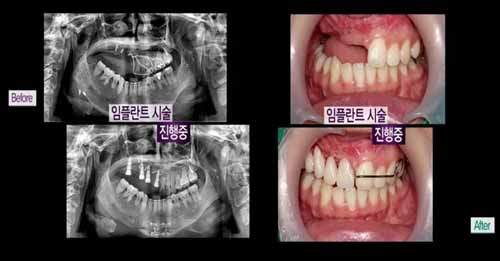

還有不見得牙齒,當然也是用假牙去補齊的

再來看一次她的整形前後比較圖

是不是差很多呢?